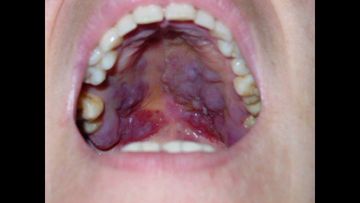

Kaposi's Sarcoma

OVIdental Go

Клиническое видео